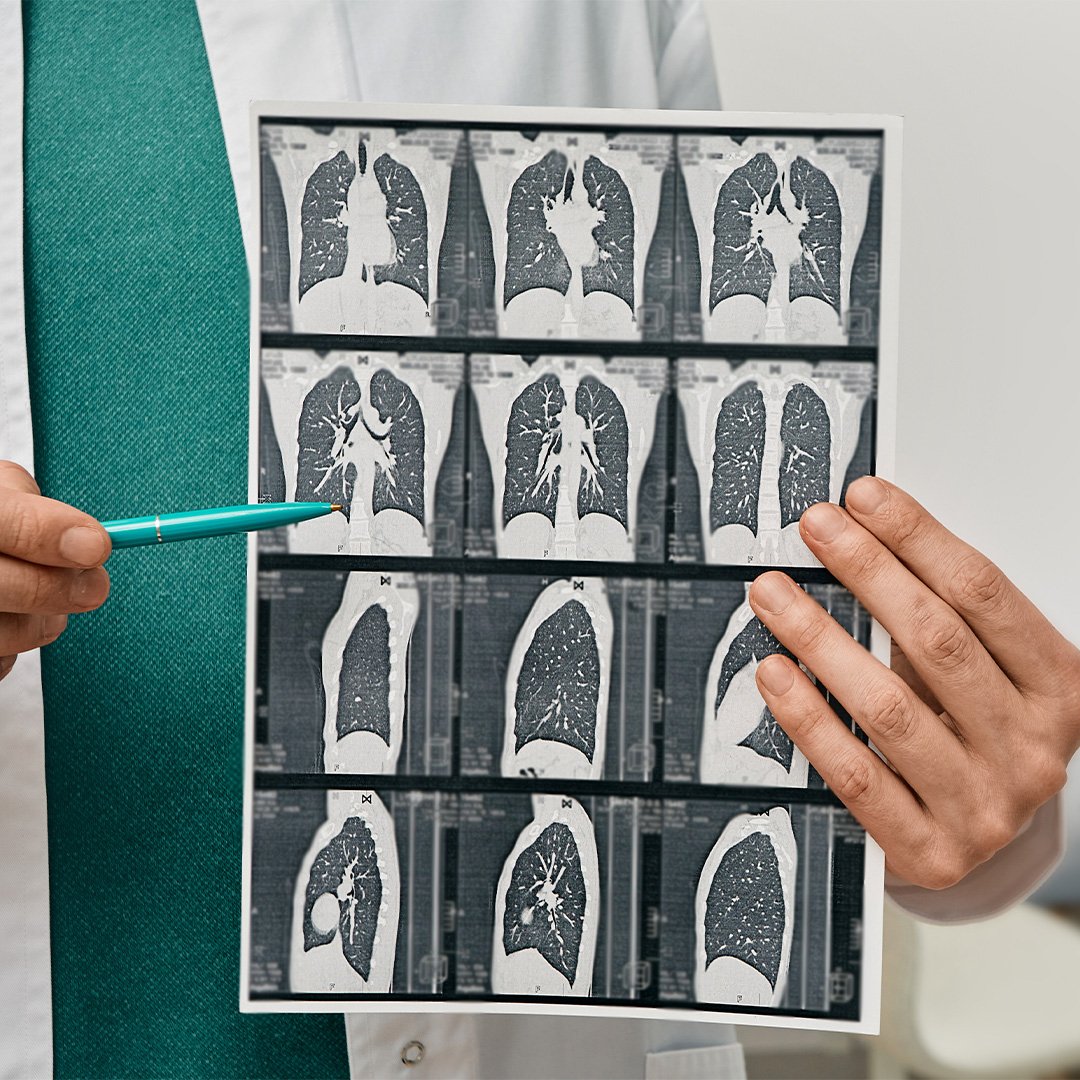

Precisión científica y calidez humana en cada examen. Somos líderes en ayudas diagnósticas de alta complejidad.

En Prodiagnóstico IPS, combinamos la experiencia de nuestros especialistas con tecnología de vanguardia para ofrecer resultados que generan confianza. Nuestra presencia estratégica en Medellín, Rionegro y la región nos posiciona como un pilar fundamental en la red de salud de Antioquia.

La claridad de la imagen define la certeza del diagnóstico. Invertimos en equipos de resonancia magnética y tomografía computarizada con software avanzado de reconstrucción 3D.